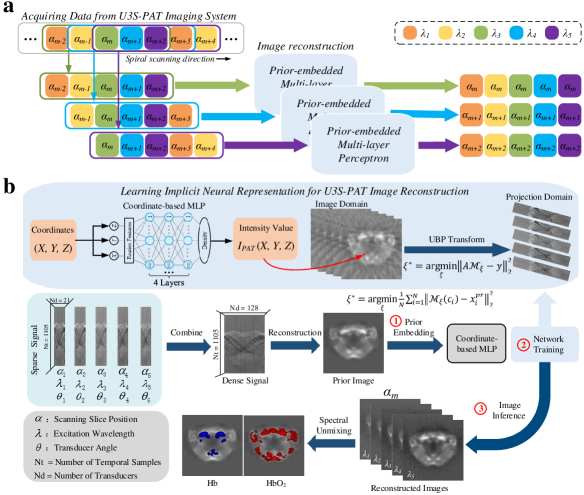

Since the transducer in cross-sectional PAT has a certain slice thickness limited by its focus, there is redundant information shared between adjacent slices if the translation distance is smaller than the slice thickness. Making use of this information should be able to improve image reconstruction. Fig.2 shows the principle of our self-supervised image reconstruction method. As shown in Fig.2 (a), in our U3S-PAT strategy, only one wavelength is used at each slice, and each slice corresponds to a single wavelength. Specifically, since the imaging wavelength loops through to , the wavelength index at is given by , where is the modulus operator and . To reconstruct images at all wavelengths, the remaining spectral information can be induced from neighboring slices. Consequently, the input to our network model is a set of data of continuous slices, and the total number of slices is determined by the number of excitation wavelengths, i.e. , such that all wavelengths are covered. The output of the network is consisting of multi-wavelength images of the center slice position. Thus, the main function of the network model is to transfer the missing spectral information from adjacent slices to the center slice.

Fig.2 (b) shows the schematic of the reconstruction network at a given tomographic position when . Considering the interlaced scanning principle of U3S-PAT, we can combine all the acquired spirally scanned signal to form a dense set of signal with a high angular coverage density. From the combined signal we can then reconstruct a fusion image that integrates information from different wavelengths, transducer rotation angles, and tomographic positions. Therefore, this fusion image has rich, high-quality structural information, and thus can be used as prior knowledge to guide image reconstruction. To do so, the weights of the MLP network are embedded with internal information from the prior image to serve as an initialization for the search target image representation. Starting from this pre-embedded initialization, the network is optimized to identify the optimal points in the function space based solely on sparsely sampled measurements.

Our method involves three steps to derive the final images. Firstly, the prior image is encoded as an implicit neural representation by embedding the entire spatial image field into network parameters. Secondly, using the prior-embedded network as initialization, for training network to learn the reconstruction of multi-wavelength data, we utilized the sparse sampling data obtained at the given slice as well as its neighboring slices acquired at different wavelengths to perform the constrained reconstruction. Finally, by traversing all spatial coordinates in the image space, the learned MLP generates the reconstructed images, i.e. images of the center slice at to . By performing the above steps at each tomographic position, a complete set of multi-wavelength images at all slices can be obtained.

2.2.1 Network architecture

The neural network in our approach is implemented as a 4-layer MLP network comprising 512 neural nodes in width. In each layer except the final layer, we employed a periodic activation function, known for its effectiveness in capturing fine details in signals [35]. The image is represented as a continuous function within the neural network. We define the network, denoted as , with the parameter , as follows:

The network function takes the normalized spatial coordinates as input and produces the corresponding intensity value as output. By mapping coordinates to image intensities, the network function encapsulates the internal information of the entire image within its parameters . Thus, we consider the network structure with parameters as a neural representation of the images because it captures the essential characteristics of the images.

2.2.2 Prior embedding

We incorporate the prior images into the network during initialization. The coordinate-based MLP network is employed to map the spatial coordinates to their corresponding intensity values in the prior images . Mathematically, this can be expressed as , where denotes the index of coordinates in the image’s spatial field. With a total of pixels in the image denoted as . The initially randomized MLP network is optimized using the following objective function:

Following the optimization process, is updated to encode the internal information of the prior images . This encoding is achieved by combining the optimized network parameters with . To maintain clarity and distinction, we denote the resulting MLP network as , representing the prior-embedded MLP network. In other words, the prior images are equivalent to the output of this embedded MLP network, denoted as .

2.2.3 Network training

Utilizing the pre-embedded MLP network and the given sparse measurements , where includes sparse sampling data for each tomographic position. We aim to train the network to acquire the neural representation of target images. The target images , being dependent on the coordinate-based MLP network and its parameter , are utilized to define the data term as , where is a data term used to measure the error between the and variables to ensure that the data is consistent with the sensor measurements. Matrix represents the forward model of the imaging system. The function is a distance metric such as L1 or L2 norm. This formulation enables the optimization of the MLP parameter space to translate into the optimization of the image space. The network undergoes training through the minimization of the L2 parametric loss, leveraging the initialization provided by the prior embedding network . Consequently, the optimization objective for the network can be expressed as follows:

To reconstruct a complete set of multi-wavelength images, we employ a joint constraint reconstruction using the sparse sampling data obtained from not only the given slice position, but also from neighboring slices acquired at multiple wavelengths. Therefore, for reconstructing multi-wavelength images of tomographic position , since its corresponding excitation wavelength is , where , the reconstruction loss for the image can be expressed as:

2.2.4 Images inference